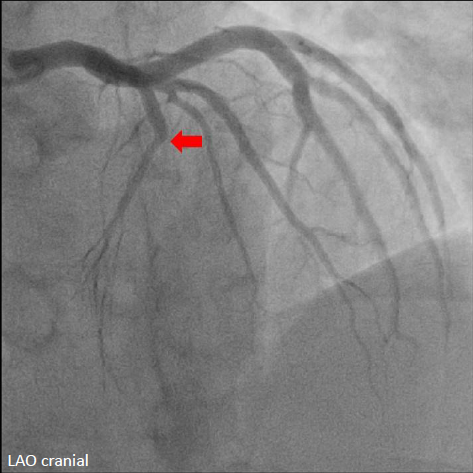

Emergent cardiac catheterization revealed patent left main coronary artery with total occlusion of the proximal left anterior descending artery (LAD). The left circumflex and right coronary arteries were patent. The culprit lesion was the proximal LAD.

The left coronary artery was engaged with an XB 3.5¡¿6 Fr guide catheter. Using a Fielder FC guidewire with a Fine-Cross microcatheter, the distal LAD was successfully accessed. Pre-dilation with a 1.5¡¿20 mm balloon demonstrated residual stenosis with poor flow. Further dilation with a 2.0¡¿15 mm balloon improved flow. Intravascular ultrasound (IVUS) revealed intramural hematoma (IMH) in the proximal-to-mid LAD. A drug-eluting stent (BMX6 2.75¡¿33 mm) was deployed from the proximal LAD (distal to the first diagonal branch) to the mid LAD, followed by proximal post-stent dilation with a 4.0¡¿12 mm non-compliant balloon at 4-16 atmospheres. Post-deployment IVUS confirmed adequate stent expansion without malapposition. Final coronary angiography demonstrated TIMI grade 3 flow.